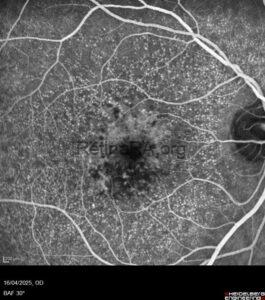

X-linked Retinoschisis

A 17-year-old male with a history of vitreoretinal surgery presented to the retina department for [...]